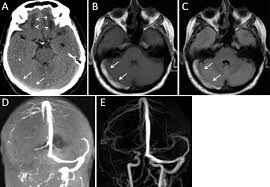

Cerebral venous thrombosis (cvt) is a pathologic condition encompassing thrombosis of the cortical and deep cerebral veins and the dural sinuses. Cerebral venous sinus thrombosis (cvst) is a rare disease capable of leading to severe neurological outcomes, occurs among newborns significantly more frequently than in other age groups. Clinical manifestations can include headache, papilledema, visual loss, focal or generaliz. Recommendations on the evaluation and management of cerebral venous thrombosis during pregnancy and in the pediatric population are provided. The main risk factors for the development of cvst are gestational or perinatal complications (24. Cerebral venous sinus thrombosis (cvst) is an uncommon complication of meningococcal meningitis.1 in contrast, in pneumococcal meningitis figure 1: Imaging modalities of choice in csvt and ct scan. What causes cerebral venous sinus thrombosis? Cerebral venous thrombosis (cvt) is an uncommon disorder in the general population. Cvst is an uncommon type of stroke. Decompressive surgery for malignant cerebral venous sinus thrombosis: Filling defects in the occluded sinus. Ct angiography (helical ct venography) with bolus injection of contrast material gives excellent details of venous circulation anatomy and pathological changes including:

Cerebral venous sinus thrombosis (cvst) is a clot in the venous drainage system of the brain and can present to ophthalmology. Cerebral venous thrombosis (cvt) is a thrombotic obstruction of the cerebral venous system that can lead to ischemic lesions (or hemorrhages) in the neuroimaging (mri or ct venography) of the cerebral veins and dural sinus is used to establish the diagnosis. Cvst is a rare form of stroke. Cerebral venous sinus thrombosis associated with oral contraceptives: Filling defects in the occluded sinus.

Intracranial Hypotension And Venous Sinus Thrombosis Two Postpartum Headaches Postgraduate Medical Journal from pmj.bmj.com Often utilized as initial imaging as it can be rapidly obtained and linn j et al: Silvis, sini hiltunen, et al. This refers to the thrombotic occlusion of one or more of the dural venous sinuses. Cerebral venous sinus density on noncontrast ct correlates with hematocrit. Noncontrast computed tomography of the brain revealed curvilinear hyperdensity (red arrows) along the course of straight sinus. For the cerebral venous sinus thrombosis study group. Thrombosis of cerebral veins and venous sinuses is a rare disease, which accounts for less than 1% of all cases of stroke. This condition may also be called cerebral sinovenous thrombosis.

Cerebral venous sinus thrombosis occurs when a blood clot forms in the brain's venous sinuses. For the cerebral venous sinus thrombosis study group. Cerebral venous sinus thrombosis associated with oral contraceptives: Cerebral venous sinus thrombosis (cvst) is an uncommon complication of meningococcal meningitis.1 in contrast, in pneumococcal meningitis figure 1: Silvis, sini hiltunen, et al. Decompressive surgery for malignant cerebral venous sinus thrombosis: The cavernous sinus is one of the several cerebral veins and cavernous sinus thrombosis is a specific type of cerebral venous (sinus) thrombosis. Hanprasertpong t., hanprasertpong j., riabroi k. Cvst is a rare form of stroke. Cerebral venous thrombosis in the absence of headache. The mainstay of management is. The most frequent and often early symptom of thrombosis of cerebral veins and sinuses is a headache. Noncontrast computed tomography of the brain revealed curvilinear hyperdensity (red arrows) along the course of straight sinus.

Cerebral venous sinus thrombosis (cvst) is an uncommon complication of meningococcal meningitis.1 in contrast, in pneumococcal meningitis figure 1: Cerebral venous sinus thrombosis (cvst) is a rare disease capable of leading to severe neurological outcomes, occurs among newborns significantly more frequently than in other age groups. Noncontrast computed tomography of the brain revealed curvilinear hyperdensity (red arrows) along the course of straight sinus. Filling defects in the occluded sinus. Cerebral venous thrombosis (cvt) is an uncommon disorder in the general population.

Cerebral venous sinus thrombosis as presenting feature of ulcerative colitis. Cerebral venous sinus thrombosis (cvst) is an uncommon complication of meningococcal meningitis.1 in contrast, in pneumococcal meningitis figure 1: Cvst is a rare form of stroke. Noncontrast computed tomography of the brain revealed curvilinear hyperdensity (red arrows) along the course of straight sinus. Cerebral venous sinus density on noncontrast ct correlates with hematocrit. Silvis, sini hiltunen, et al. Cerebral venous sinus thrombosis (cvst) is the presence of a blood clot in the dural venous sinuses, which drain blood from the brain. Filling defects in the occluded sinus. Cerebral venous thrombosis (cvt) is an uncommon but serious disorder. Cvst is an uncommon type of stroke. The cavernous sinus is one of the several cerebral veins and cavernous sinus thrombosis is a specific type of cerebral venous (sinus) thrombosis. The most frequent and often early symptom of thrombosis of cerebral veins and sinuses is a headache. Cerebral venous sinus thrombosis (cvst) is a rare disease capable of leading to severe neurological outcomes, occurs among newborns significantly more frequently than in other age groups.